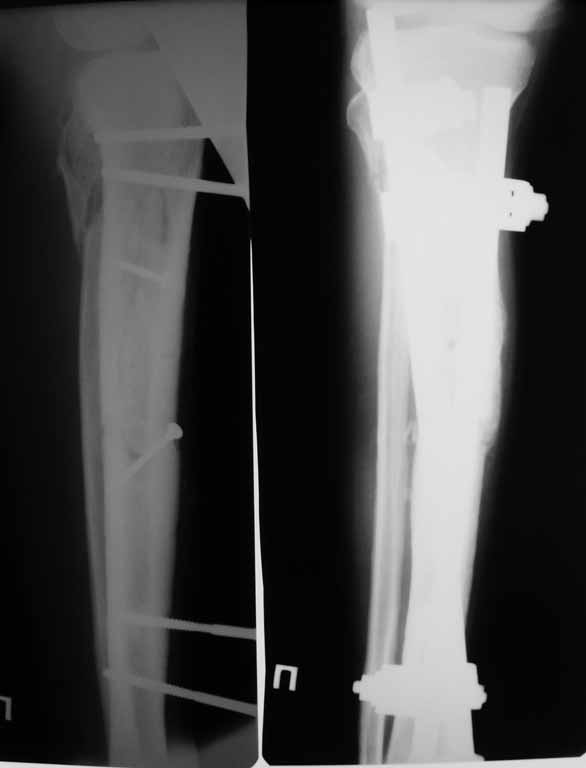

Привожу пример: Пациент с открытой тяжелой ЧМТ.

Диагноз при поступлении: Открытый оскольчатый перелом свода и основания черепа,субдуральная гематома, ушиб головного мозга тяжелой степени. Открытый оскольчатый перелом костей правой голени. Шок 3 Кома 3

По тяжести ЧМТ ( по данным РКТ) выжить был не должен в принципе.

При поступлении оперирован : трепанация, ПХО, остеосинтез голени.

Консолидация в аппарате внешней фиксации к 2 месяцам. Аппарат снят через 2,5 месяца.

Фото в приложении.